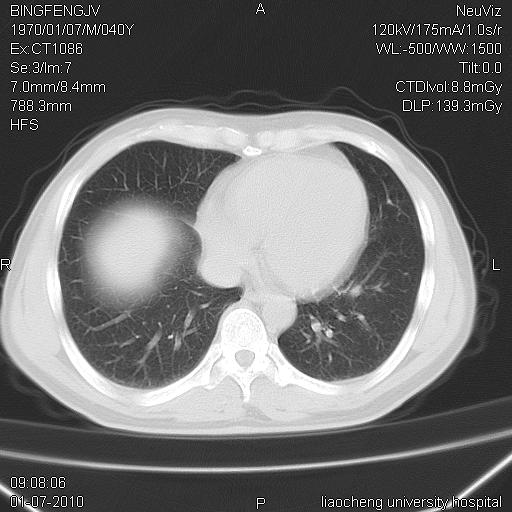

标题: CT23764B:男 40 肺部CT [打印本页]

标题: CT23764B:男 40 肺部CT

治疗2周后

炎症性病灶,继发性改变。

考虑左肺上叶近胸膜下炎症并肺气囊形成。

炎症,大部吸收。